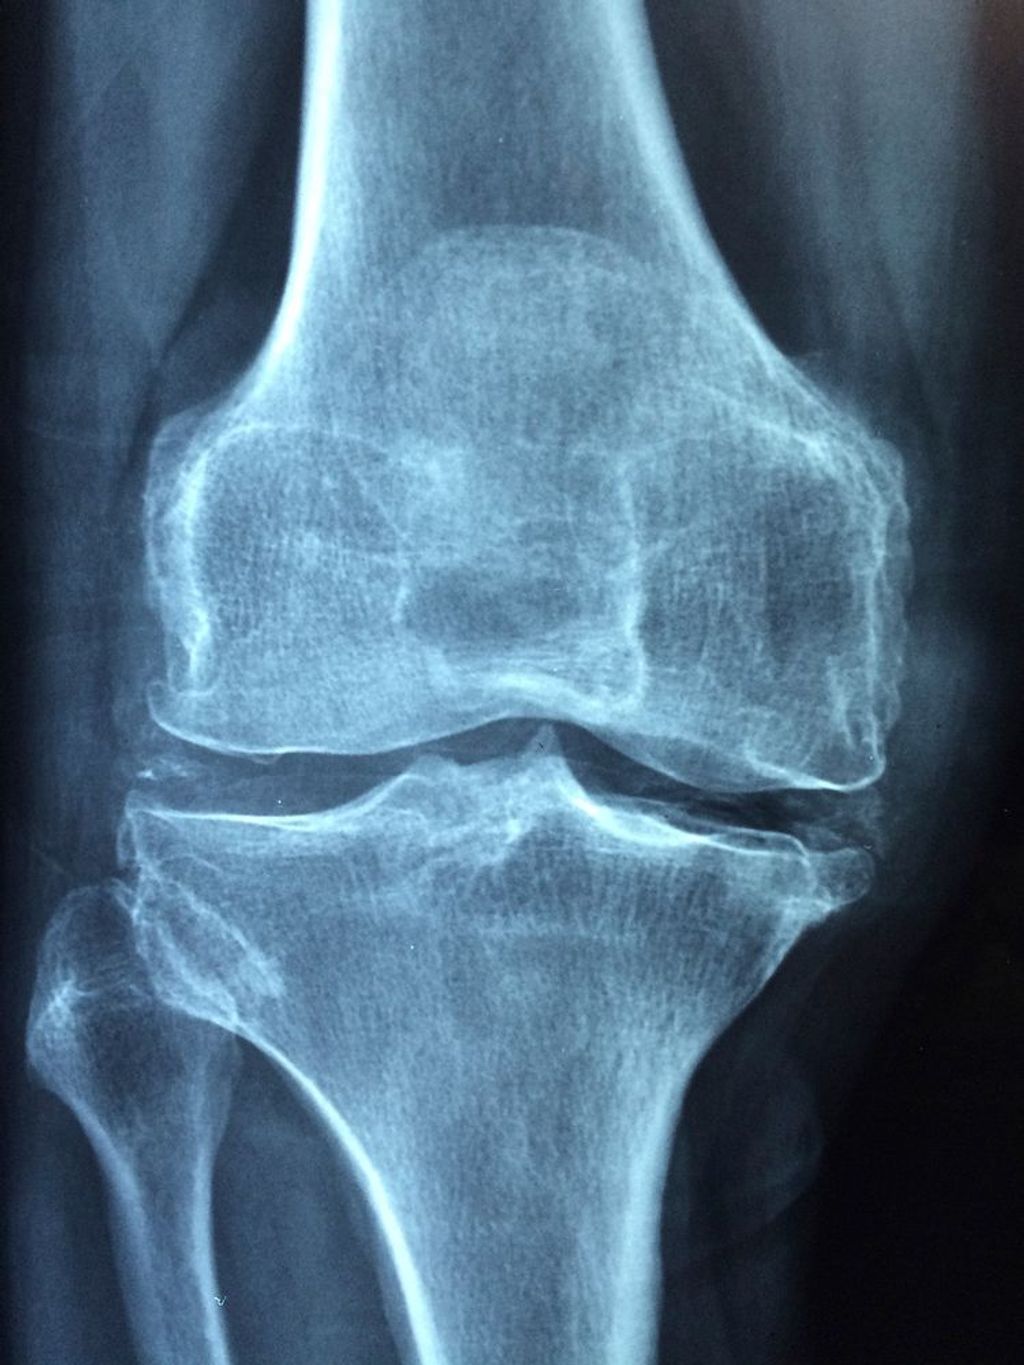

The clinical presentation of osteoarthritis of the knee often includes gradual onset of pain, stiffness, and functional limitations. Patients may experience discomfort during weight-bearing activities and report a decrease in range of motion. Additionally, joint tenderness and swelling may be observed upon physical examination. Radiographic evidence of joint space narrowing and osteophyte formation is commonly associated with the clinical presentation of OA knee. These manifestations contribute to the overall impact on the patient’s quality of life and functional ability.

Surgical Interventions for OA Knee

![]()